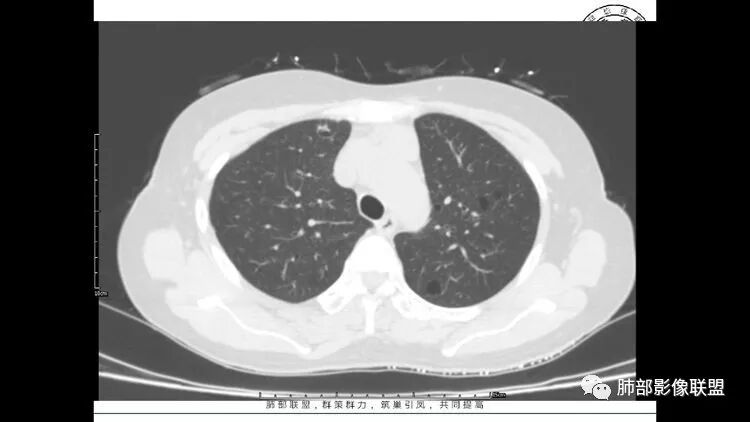

老年女性,眼炎入院,血常规正常,双肺多发囊状影,病变随机分布,形态单一,与血管关系密切,考虑LIP。左下肺混合GGO,边界尚清,贴近囊腔,鉴别腺癌。炎症指标无异常暂不考虑感染性病变。

胸CT:1.双肺多发囊性变,以中下肺为主,病变边缘可见肺动脉,部分囊内可见分隔及肺动脉,双下部分肺野周围可见小叶中心结节及树丫征。

2 左肺上叶尖后段 右肺上叶前段 右肺下叶外基底段 结节影,边界清楚,可见柔软毛刺,左肺下叶后基底段混合密度影。

3.纵隔淋巴结肿大?,以主动脉弓为界向上向下增大。

双肺多发磨玻璃结节,其内可见空腔,周围边界清晰,多发囊,左肺实性结节。考虑间质性肺炎,LIP可能性大。鉴别腺癌。

患者中年女性,因右眼红痛1天就诊。胸CT:双肺多发囊性变及结节影,囊以中下肺为多,部分囊内可见分隔及肺动脉,结节部分为实性,部分为混合性,边缘光滑,未见明显毛刺、棘突、胸膜牵拉及血管集束征象。双中下可见支气管扩张及树丫征。淋巴结无明显肿大。综合考虑:一元淋巴细胞间质性肺炎。多元鉴别肺腺癌并转移等恶性病变。

中年女性,双肺多发囊性变,以中下肺为主,病变边缘可见肺动脉,部分囊内可见分隔及肺动脉,左肺上叶较大结节,可见分叶、月牙铲,左肺下叶、右肺中叶磨玻璃病灶,边界清楚,内有空泡,结节,可见尖后段 右肺上叶前段 右肺下叶外基底段 结节影,边界清楚,纵隔淋巴结肿大,

中年女性,因“角膜炎”入院,自用眼液2年,(眼干?)肺部:双肺多发类圆形薄壁气囊+实性结节+GGO,下肺分布为主,纵隔淋巴结肿大,考虑淋巴系统增殖,LIP可能性大,可能继发于干燥综合症;左肺下叶的混合磨玻璃结节形迹可疑,边界清晰,内部疑似空泡,扩张扭曲支气管,极像肺癌,伴双肺转移?待排吧

左肺下叶混杂密度病灶,其内可见空泡,周围ggo清楚,考虑浸润性腺癌。双肺散在多发薄壁囊腔和实性结节,以胸膜下及血管旁分布位于,气囊可见血管贴边征,双肺小叶间隔及中央间质增厚,局部可见磨玻璃影及树芽征,纵隔内淋巴结肿大,考虑LIP

综上,考虑左下肺浸润性腺癌+LIP

LIP影像重要线索一句话:

双肺下叶分布为主的间质改变(磨玻璃影、小叶间隔增厚)、散在气囊影(常有血管贴边)、边界不清小结节